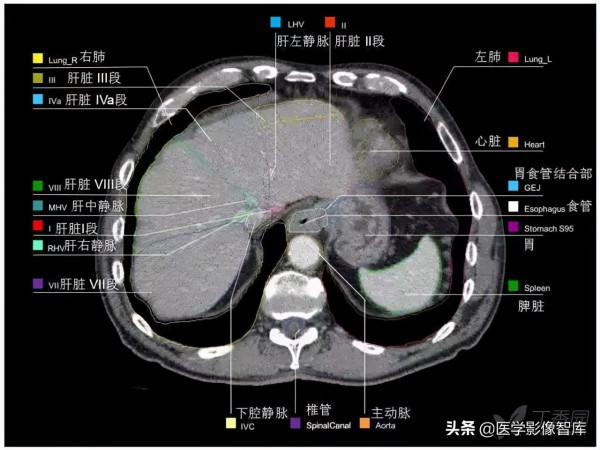

腹部CT